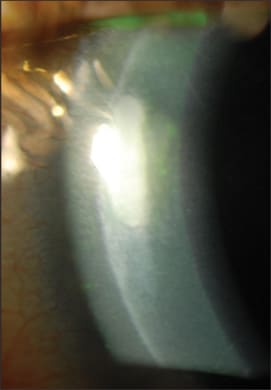

Mild punctate staining after LASIK.